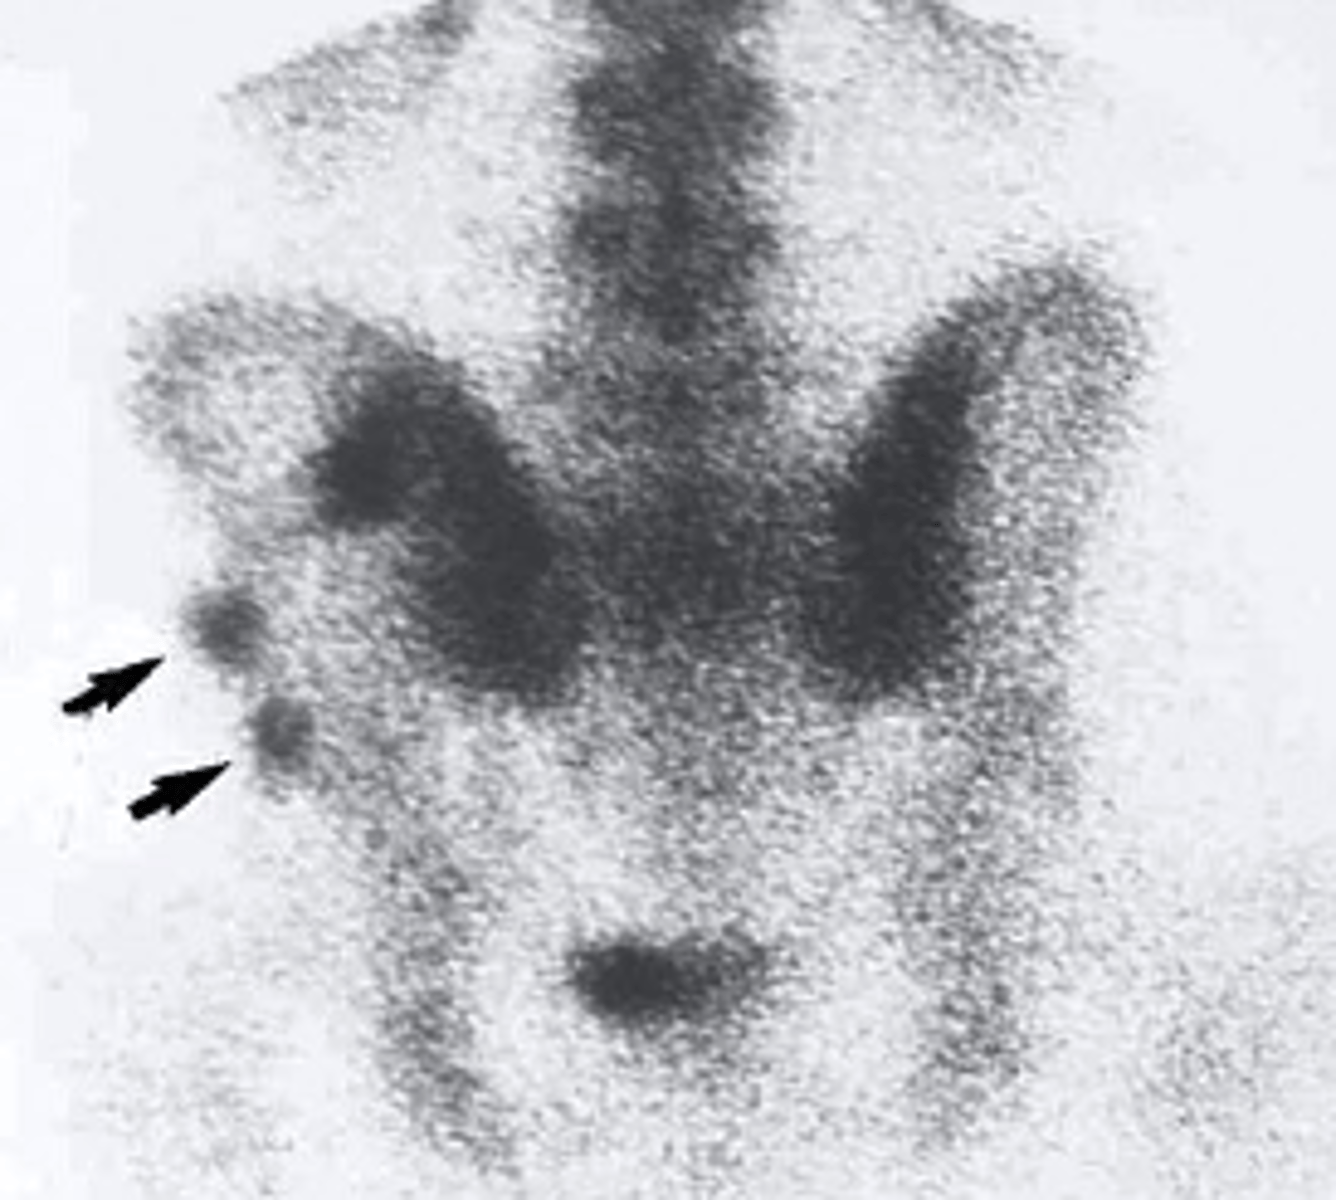

what occurs with a radionuclide bone scan

radiopharmaceutical substance is injected into the patient and collects in areas of increased bone activity and will appear as black/dark for a hot spot of activity

Radionuclide bone scan

what type of imaging study is this?

a. Radionuclide bone scan

b. ultrasound

c. PET scan

d. mammogram

what is a radionuclide bone scan used to view

-subtle fx

-primary and metastatic tumors

-infections

-AVN

-metabolic bone disease

-unexplained bone pain

-epiphyseal growth plates

-areas of arthritis

multiple skeletal metastases

which of the following would be the correctly associated image findings?

a. bone fracture

b. epiphyseal plates

c. multiple skeletal metastases

d. Blood Clots